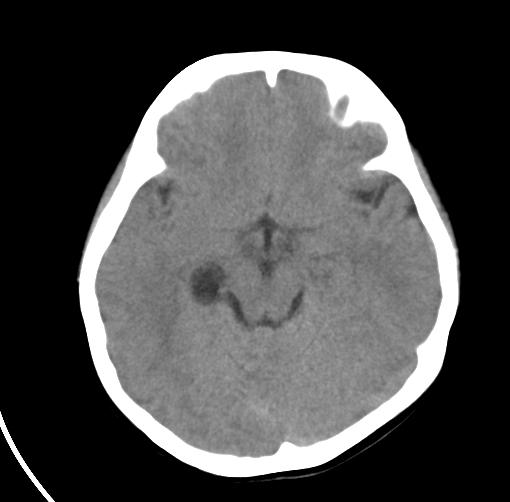

以下是引用zjzjr在2007-7-31 22:25:00的发言:[br]考虑脉络裂囊肿

以下是引用sunjh2266在2007-7-31 23:35:00的发言:[br]脉络膜裂,是胚胎发育过程中脉络襞突入侧脑室下角构成脉络丛时形成,位于丘脑下部与海马之间,走行与海马平行。脉络裂内侧通于环池,外侧为侧脑室下角,前面是海马钩及杏仁体,后部与海马沟交通。脉络裂内有参与组成侧脑室脉络丛的脉络膜前动脉及脉络膜后外动脉及其分支走行。[br] mri轴位像,在大脑脚的前外侧多能显示脉络裂的前部,呈左右走行的含脑脊液间隙,前后内外分别与杏仁体、海马、海马钩及侧脑室下角相邻(图1);冠状位像,在扫及脑干的多个层面上,脉络裂均可被清晰显示,因而是显示脉络裂的最佳扫描方式。偏前的部分层面还可见到呈切迹状的海马沟走行于海马旁回内上方;矢状位像,海马旁回上方可见一分叉状裂隙,类似一斜卧的“入”字,接近水平走行的一撇为脉络裂,而由后上向前下走行的一捺为从扣带沟延续而来的海马沟。[br] [br]